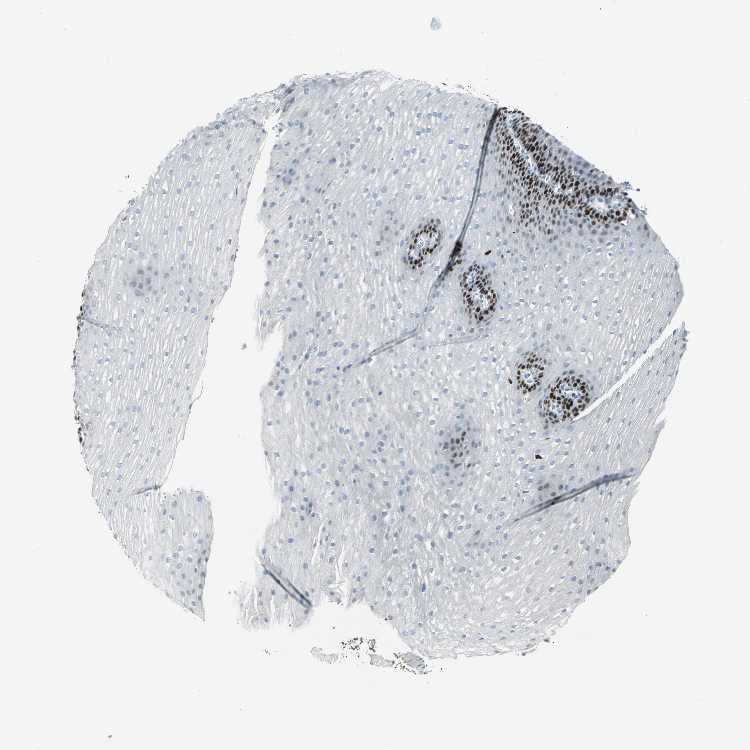

ESOPHAGUS - Antibody stainingi

Antibody staining in the annotated cell types in the current human tissue is reported as not detected, low, medium, or high, based on conventional immunohistochemistry profiling in selected tissues. This score is based on the combination of the staining intensity and fraction of stained cells.

Each image is clickable and will lead to virtual microscopy that enables deeper exploration of all samples and also displays staining intensity scores, fraction scores and subcellular localization as well as patient and tissue information for each sample.

Antibody HPA004873Antibody CAB004497

Squamous epithelial cells MediumHigh